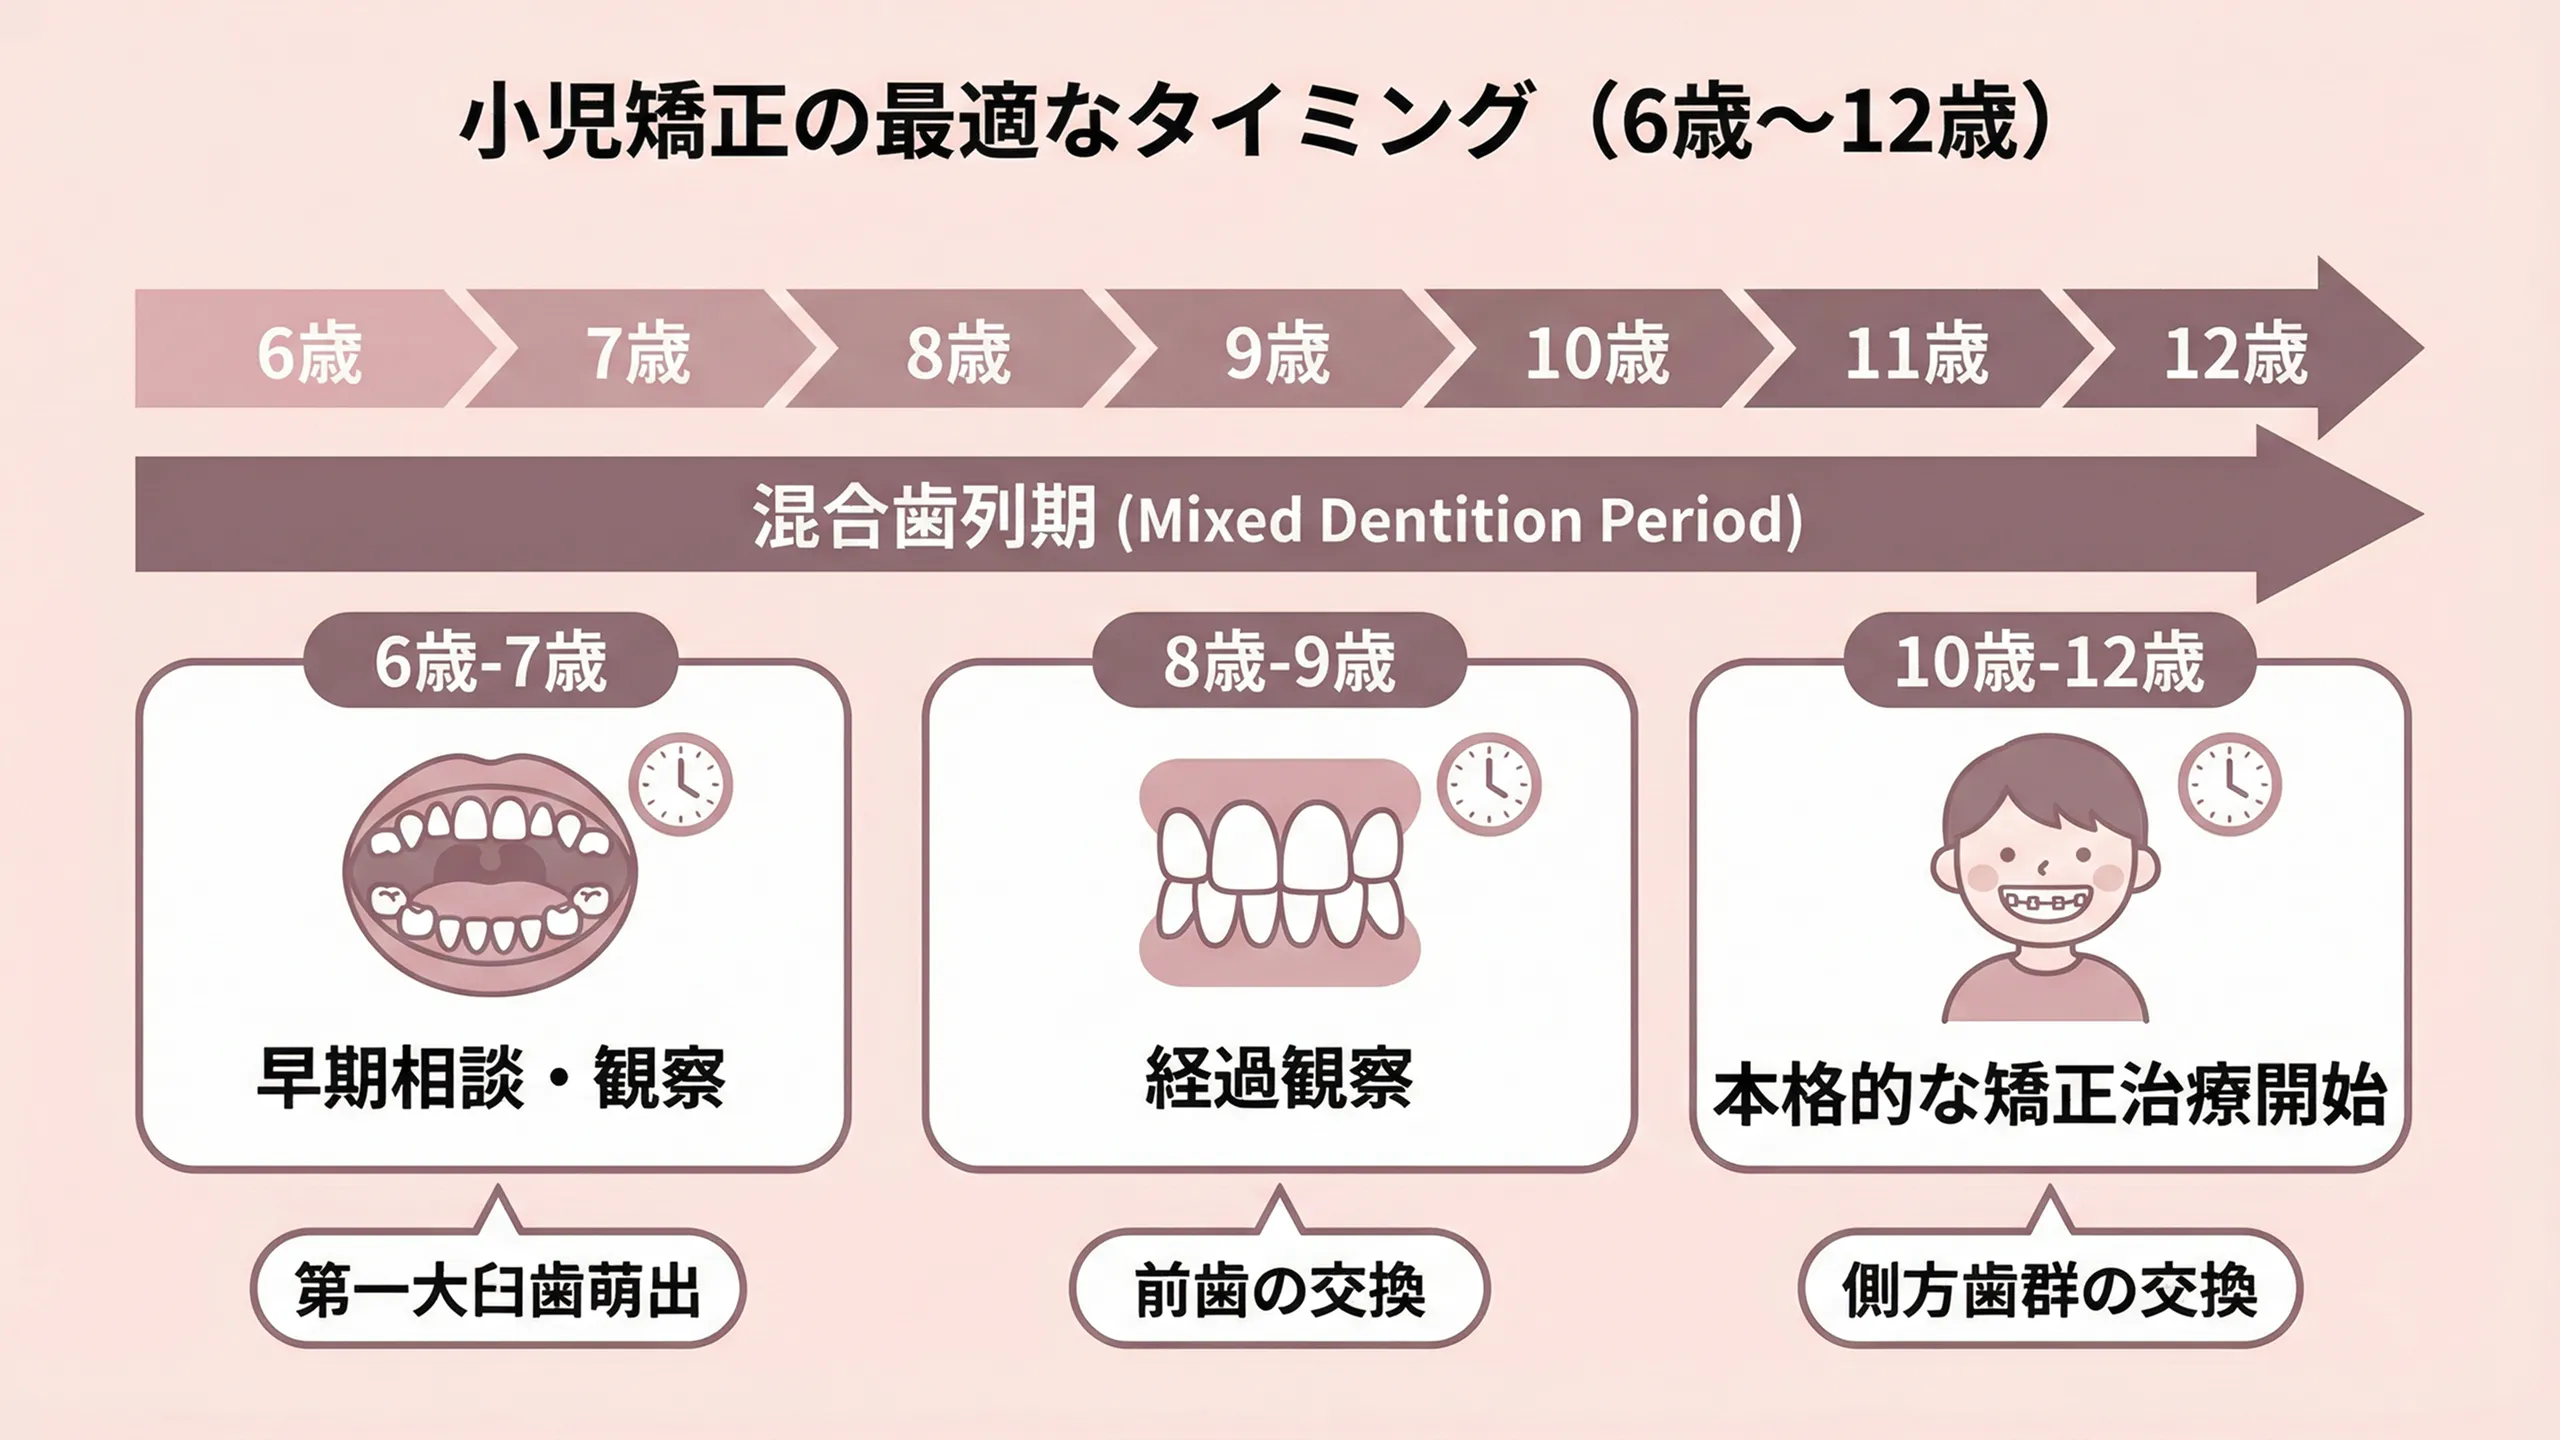

治療を始めるベストタイミングと治療期間の目安

小児矯正を始めるベストなタイミングは、上の前歯4本が生えそろった直後(7〜9歳ごろ)です。この時期はあごの骨がやわらかく、成長をうまく利用しながら歯並びを整えることができます。

ただし、かみ合わせのズレ(交叉咬合:こうさこうごう)や、口がいつも開いている(口呼吸)が目立つお子さまは、もう少し早めの治療が必要な場合もあります。

第一期のベストなタイミングは?

小児矯正(第一期治療)を始めるベストなタイミングは、上の前歯4本が生えそろった直後(7〜9歳ごろ)です。この時期はあごの成長が活発で、歯を動かしやすく、治療の効果が出やすい「ゴールデンタイム」と言えます。

前歯4本が生えそろうと、将来の歯並びの傾向がある程度わかるようになります。このタイミングで矯正を始めることで、あごの成長を利用しながら効率よく歯並びを整えられます。